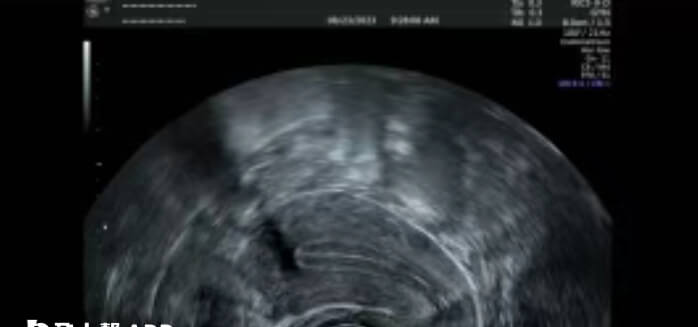

B超单上三线征是指B超检查子宫的时候,一般在子宫内膜分泌早期出现,说明子宫内膜发育良好,子宫内膜三线征就是子宫内膜与子宫肌层之间形成高回声的外侧线两层,子宫内膜表面清晰的高回声中心线。

A型内膜有明确的“三线征”,三条白线清晰连续,中间夹了两层黑色的内膜组织,如同一个“三明治”;若内膜三线征消失,则为C型内膜;而B型内膜则介于A型和C型之间,能够看到三线征,但不如A型内膜表现的典型。